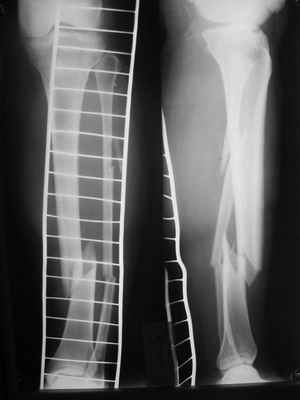

Здравствуйте уважаемые коллеги. Позвольте поделиться опытом применения интрамедуллярного остеосинтеза большеберцовой кости имплантатами компании ?Остеомед" с запатентованной прицельно-навигационной системой для дистального блокирования ?Интерлок". Для определения длинны и диаметра стержня использовали линейку-шаблон, позволяющей с легкостью рассчитать длину и диаметр стержня с проекцинно искаженными размерами, как конечности, так и линейки-шаблона.Дистракцию производили с помощью спицевого дистрактора с последующей закрытой репозицией отломков винтами Шанца. Все основные этапы производили по методике АО, гарантированное дистальное блокирование достигается за счет центрирования отверстий, путем контролирования смещения стержня в костномозговом канале в сагиттальной плоскости. Клинический пример:Больная Я. 45 лет, пострадала в результате случайного падения на улице 19.12.2005., имеет место открытый 1 степени перелом обеих костей левой голени со смещением отломков.произведена закрытая репозиция перелома с последующим введением стержня (на данном этапе производился рентген-контроль)Убедившись в достаточной репозиции перелома, произведено дистальное и проксимальное блокирование интрамедуллярного стержня.Общее время затраченное на оперативное вмешательство составило 45 минут.

Ну и наверно уже результаты есть, с декабря прошлого года-то?